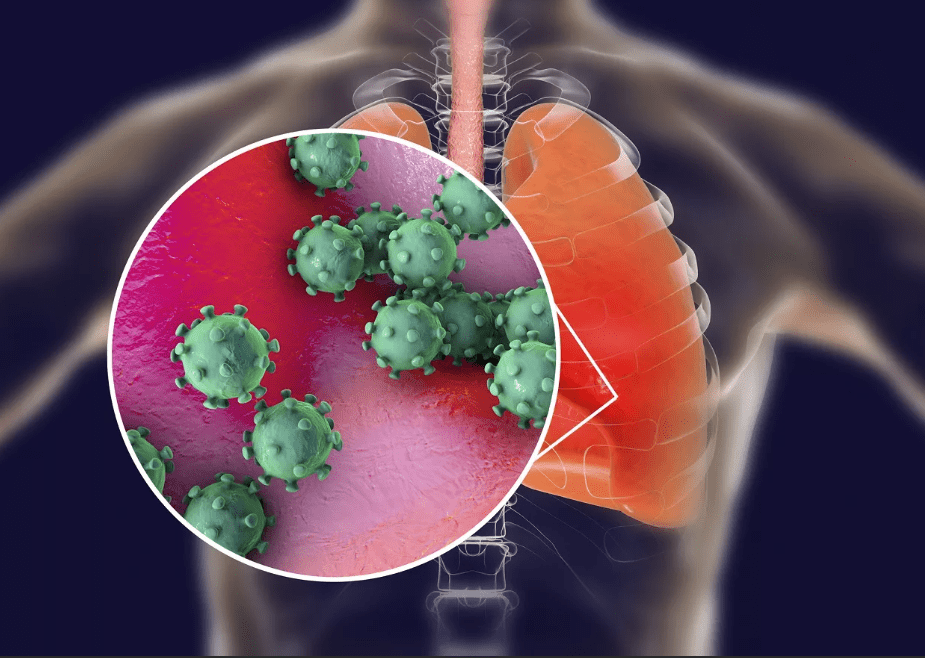

Если она вызвана COVID-19, то процесс воспаления проходит по-другому. Причиной становятся не бактерии, а вирус. Он нарушает привычную работу альвеол. В них накапливается не только жидкость, но и отмершие клетки. При таком типе воспаления поражаются уже все легкие, а не их части.

При обычной пневмонии лечение основывается на приеме антибиотиков. При воспалении легких, вызванном коронавирусной инфекцией, надо в первую очередь справиться с вирусом SARS-CoV-2. Связь COVID-19 с воспалением легких прослеживается, но это не одно и то же.

Воспаление легких может развиться и без вирусной инфекции. Пневмонию вызывает множество возбудителей.